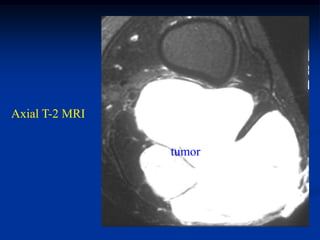

Case #1198                Axial T-2 MRI

62 year male with well-differentiated liposarcoma thigh

Coronal T-2 MRI